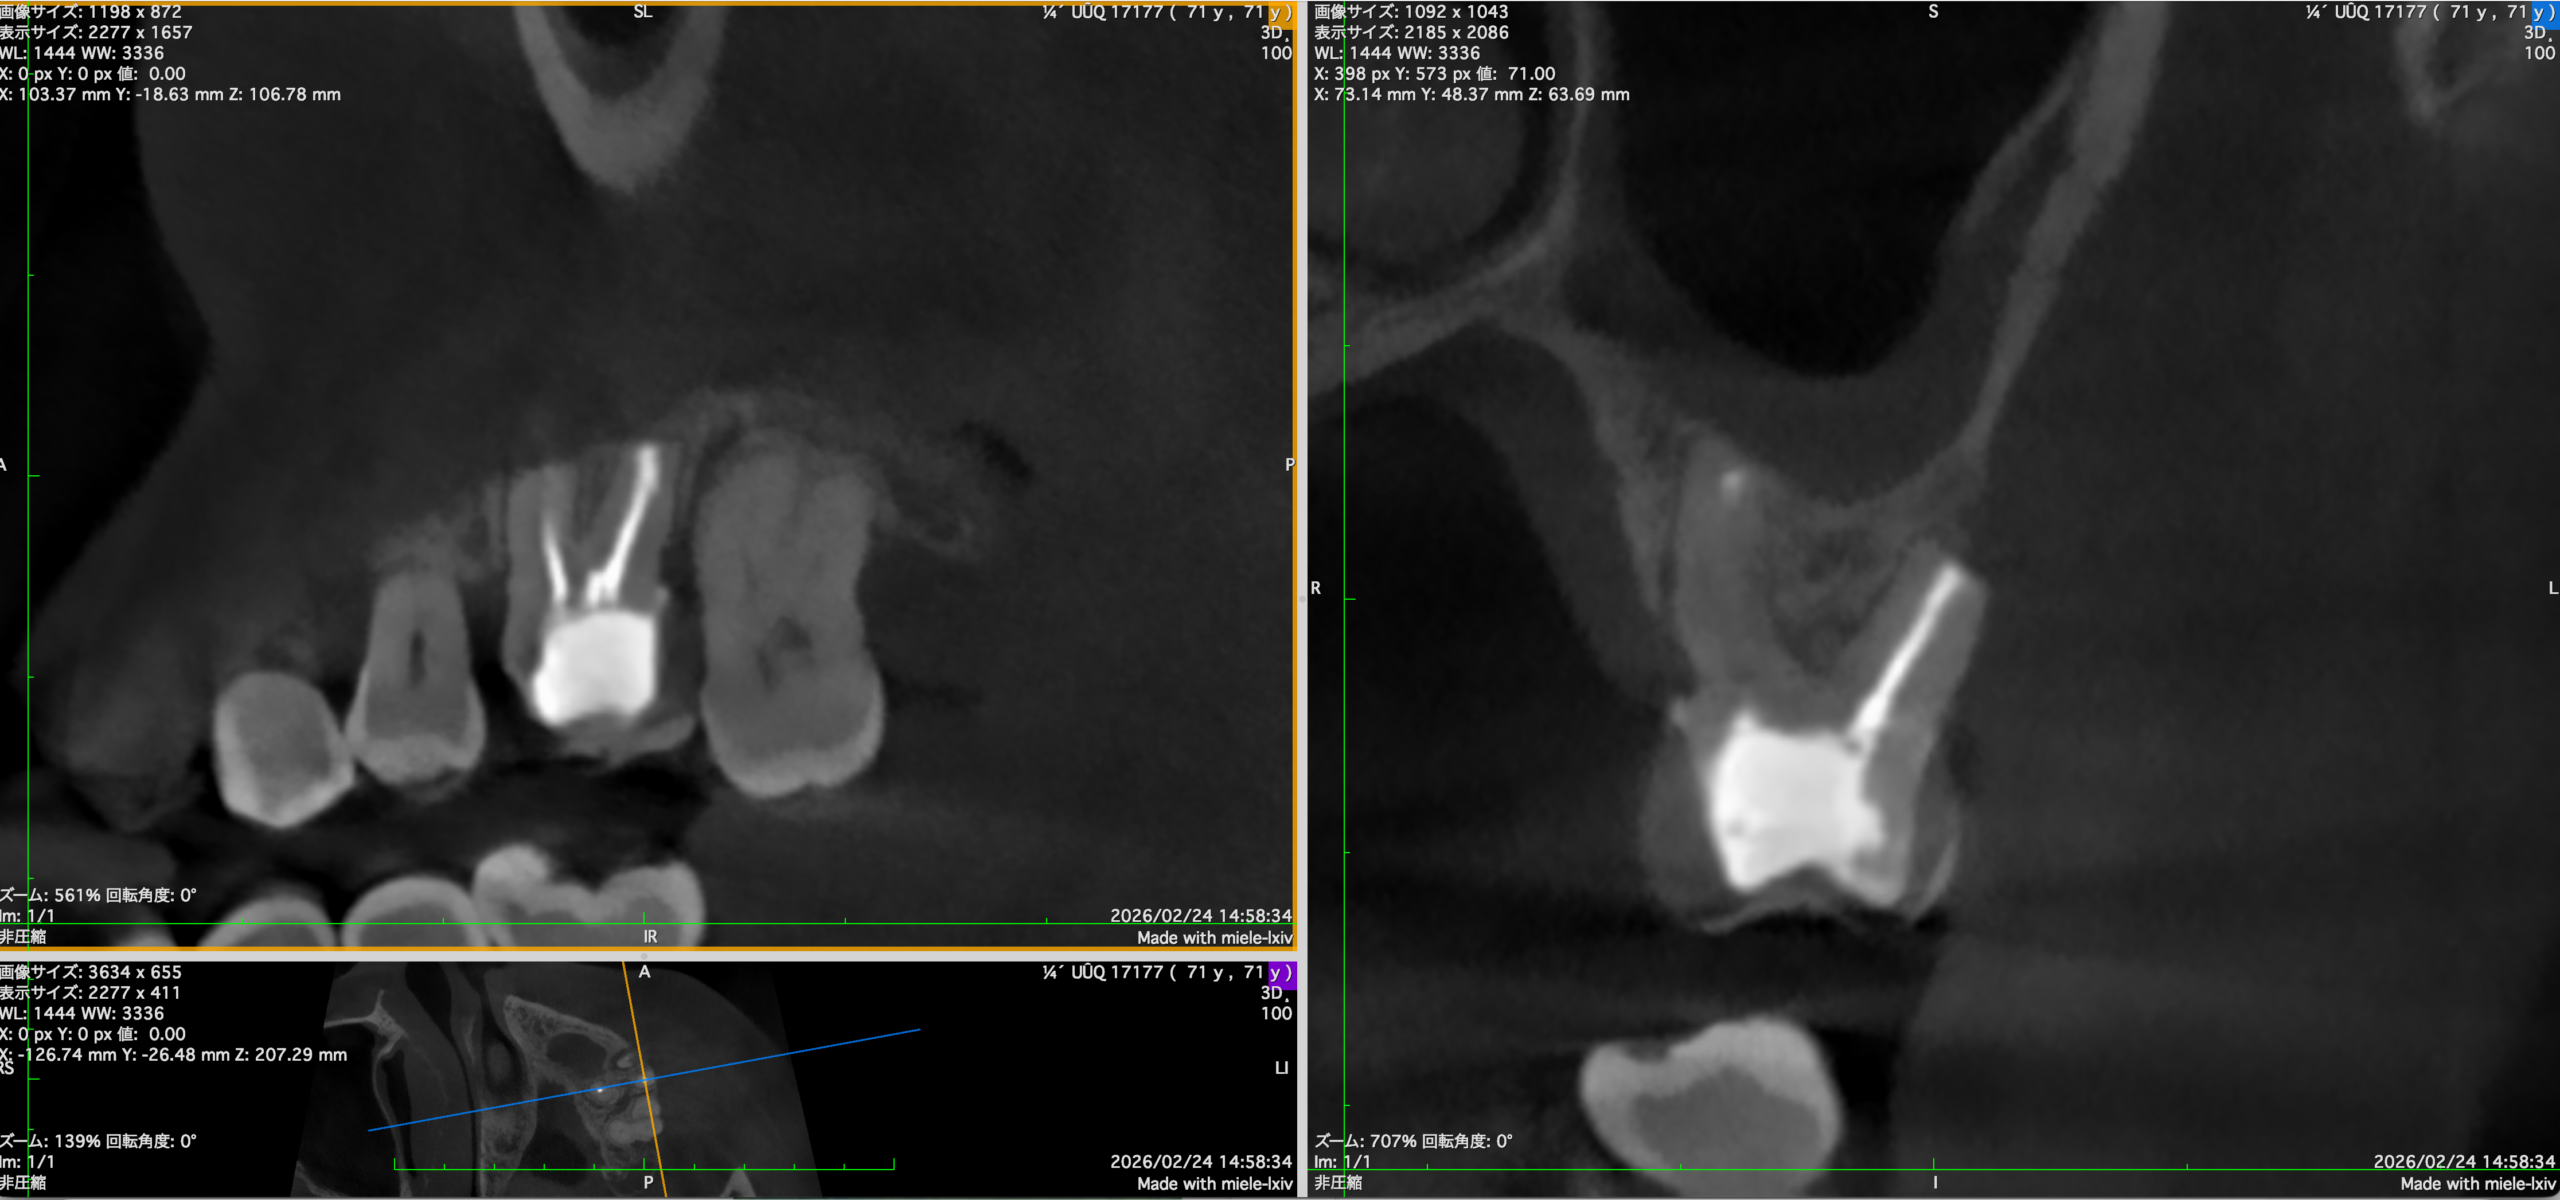

#14 MB+DB Apicoectomy 6M recall(2026.2.27)

Sinus tractと圧痛は消失したようだ。

画像判断は以下である。

MB

DB

P

半年前の術後と比較した。

術後の骨欠損は大きく回復している。

が、まだ道半ばだ。

ということでかかりつけ医の先生には最終補綴の装着を依頼した。

次回はもう半年後の1yr recallである。